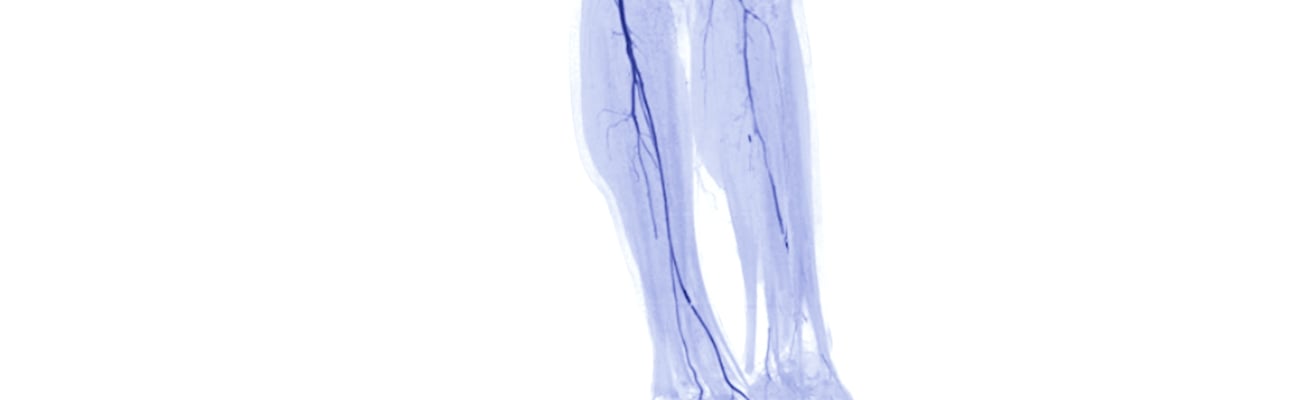

5 Tips: Risk reduction in peripheral arterial disease